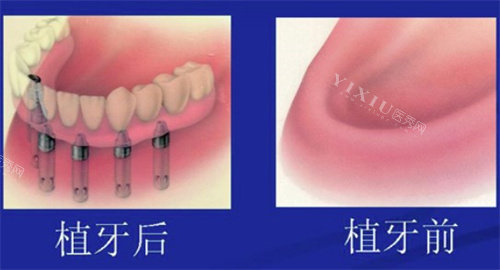

种植牙不是“一颗一颗种”,而是像搭积木一样需要整体设计。32颗牙的种植方案直接影响总价:

全口半固定种植:上下颌各植入2-4颗种植体,通过球帽或杆卡连接活动假牙,总价约6-8万元。适合牙槽骨萎缩重度的老年人,但咀嚼力有限,啃苹果需谨慎。

All-on-4/6即刻负重:上下颌各植入4或6颗种植体,当天装临时牙冠,总价约12-15万元。一位北京患者在私立医院选择All-on-6,用韩国奥齿泰植体+国产全瓷冠,总价13.8万元,术后3天啃排骨无压力。

传统全口种植:32颗牙逐颗植入,总价可达18万元以上。适合年轻患者或对咀嚼力要求极高的人群,但手术创伤大、改善期长,需谨慎选择。